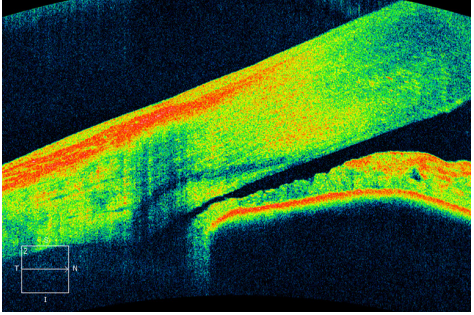

急性闭角型青光眼LPI前周边虹膜明显膨隆,

小梁网与周边虹膜间隙较窄(图1),LPI后周边虹膜轻度膨隆或者平坦(图2),小梁网与周边虹膜间隙

明显变宽。

图1 急性闭角型青光眼LPI前OCT扫描房角图

Figure 1 OCT scanning figure corner of acute angle closure

glaucoma before LPI